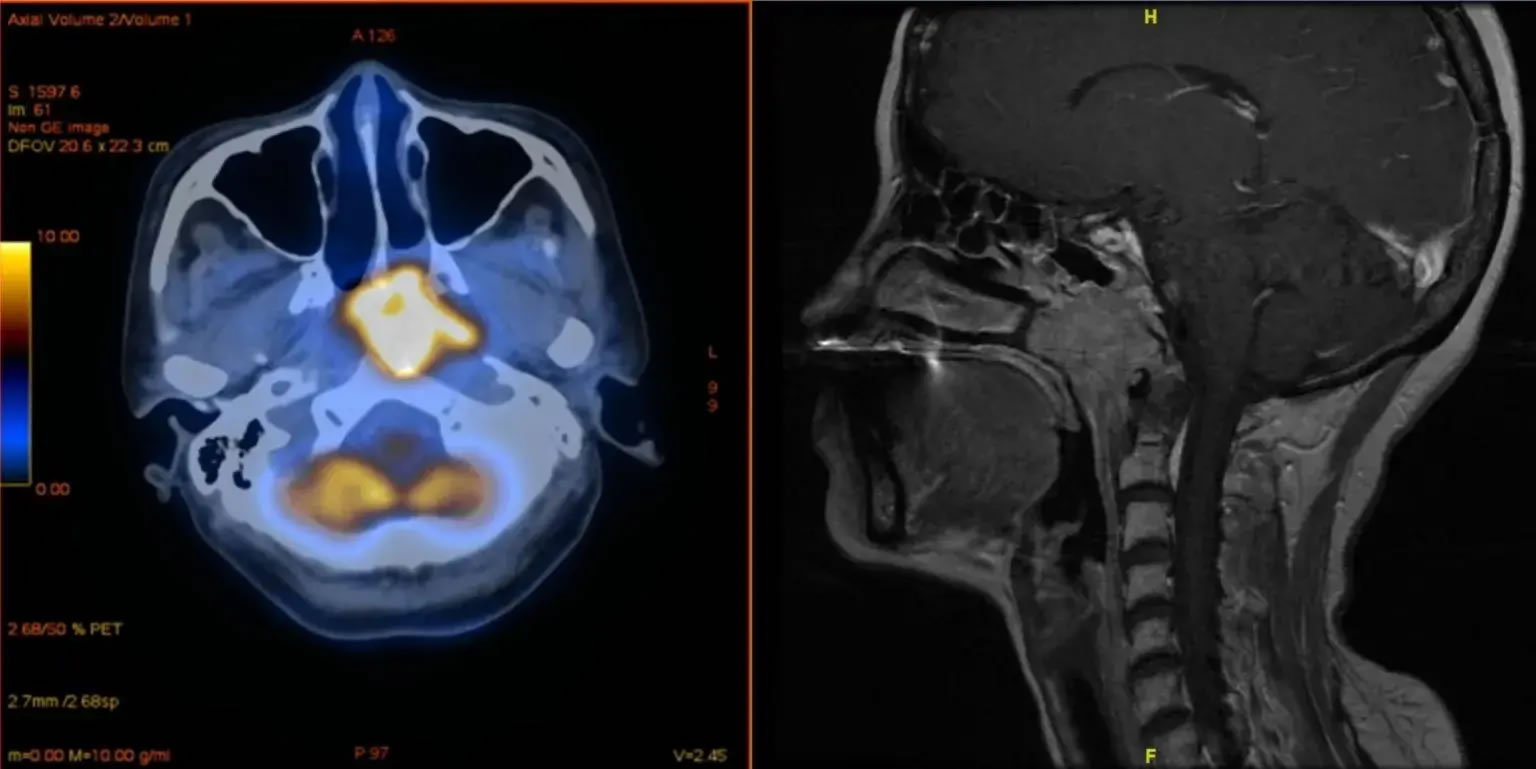

COVID-19疫苗接种对鼻咽癌疗法产生不利影响的担忧似乎是没有根据的。图像来源: Y.J. Hua / 中山大学癌症中心

鼻咽癌是一种在鼻咽部组织中形成恶性(癌症)细胞的疾病。鼻咽是鼻子后面的喉咙上部。鼻咽两侧各有一个开口通向耳朵。